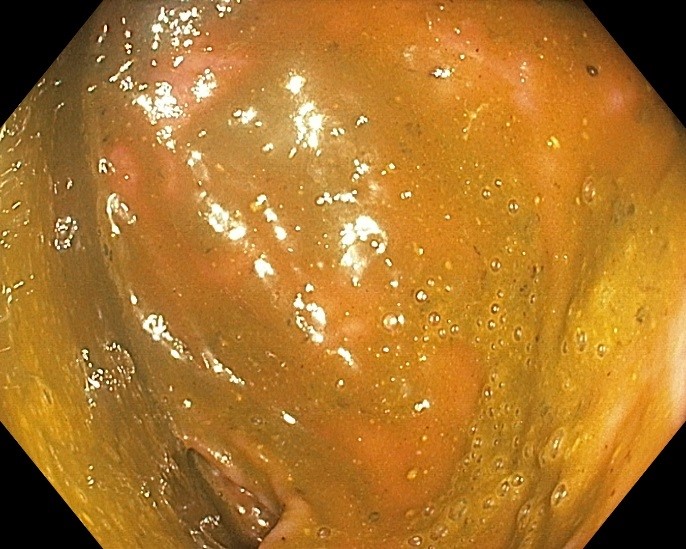

Колоноскопия является золотым стандартом диагностики и малоинвазивного лечения заболеваний толстой кишки, в том числе раннего рака и его предшественников (полипов). В целях профилактики рака толстой кишки колоноскопия показана всем после 40 лет, в среднем каждые 5 лет. Для достижения качественной подготовки толстой кишки к эндоскопическому исследованию и/или операции крайне важно строгое соблюдение всех этапов данных рекомендаций.

Некачественная подготовка толстой кишки резко снижает возможности эндоскопической диагностики (исследование будет не информативным!), что может потребовать повторной подготовки и проведения повторного исследования!

Соблюдение рекомендаций позволяет качественно провести исследование и выявить даже небольшие полипы

Соблюдение рекомендаций позволяет качественно провести исследование и выявить даже небольшие полипы